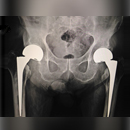

Knee, Hip and Shoulder Replacements